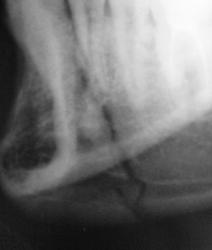

Зашинировали

У этого 3 г. назад нелеченная травма, теперь остеомиелит